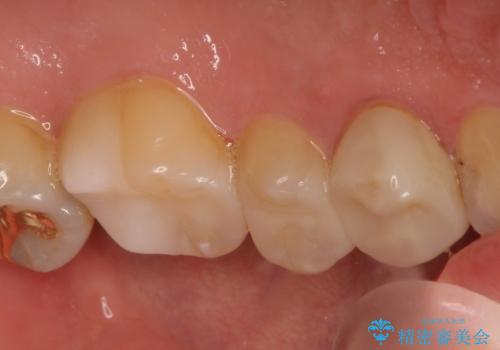

- 定期健診にて虫歯が見つかった患者さんです。他院で保険治療(CR、プラスチック)したところとまだ処置されていないところが虫歯になっていました。

セラミックインレーで治療しました。

以前保険治療で治したところが再び虫歯になっていました。保険治療で使用される材料は主にプラスチックなので必ず劣化がおきます。再治療のリスクを減らすために、セラッミックインレーで治療を行いました。セラミックインレーには劣化がほとんどありません。当院ではシリコンで型取りを行っているので、適合が良い被せものが出来き再治療のリスクを減らすことが出来ます。